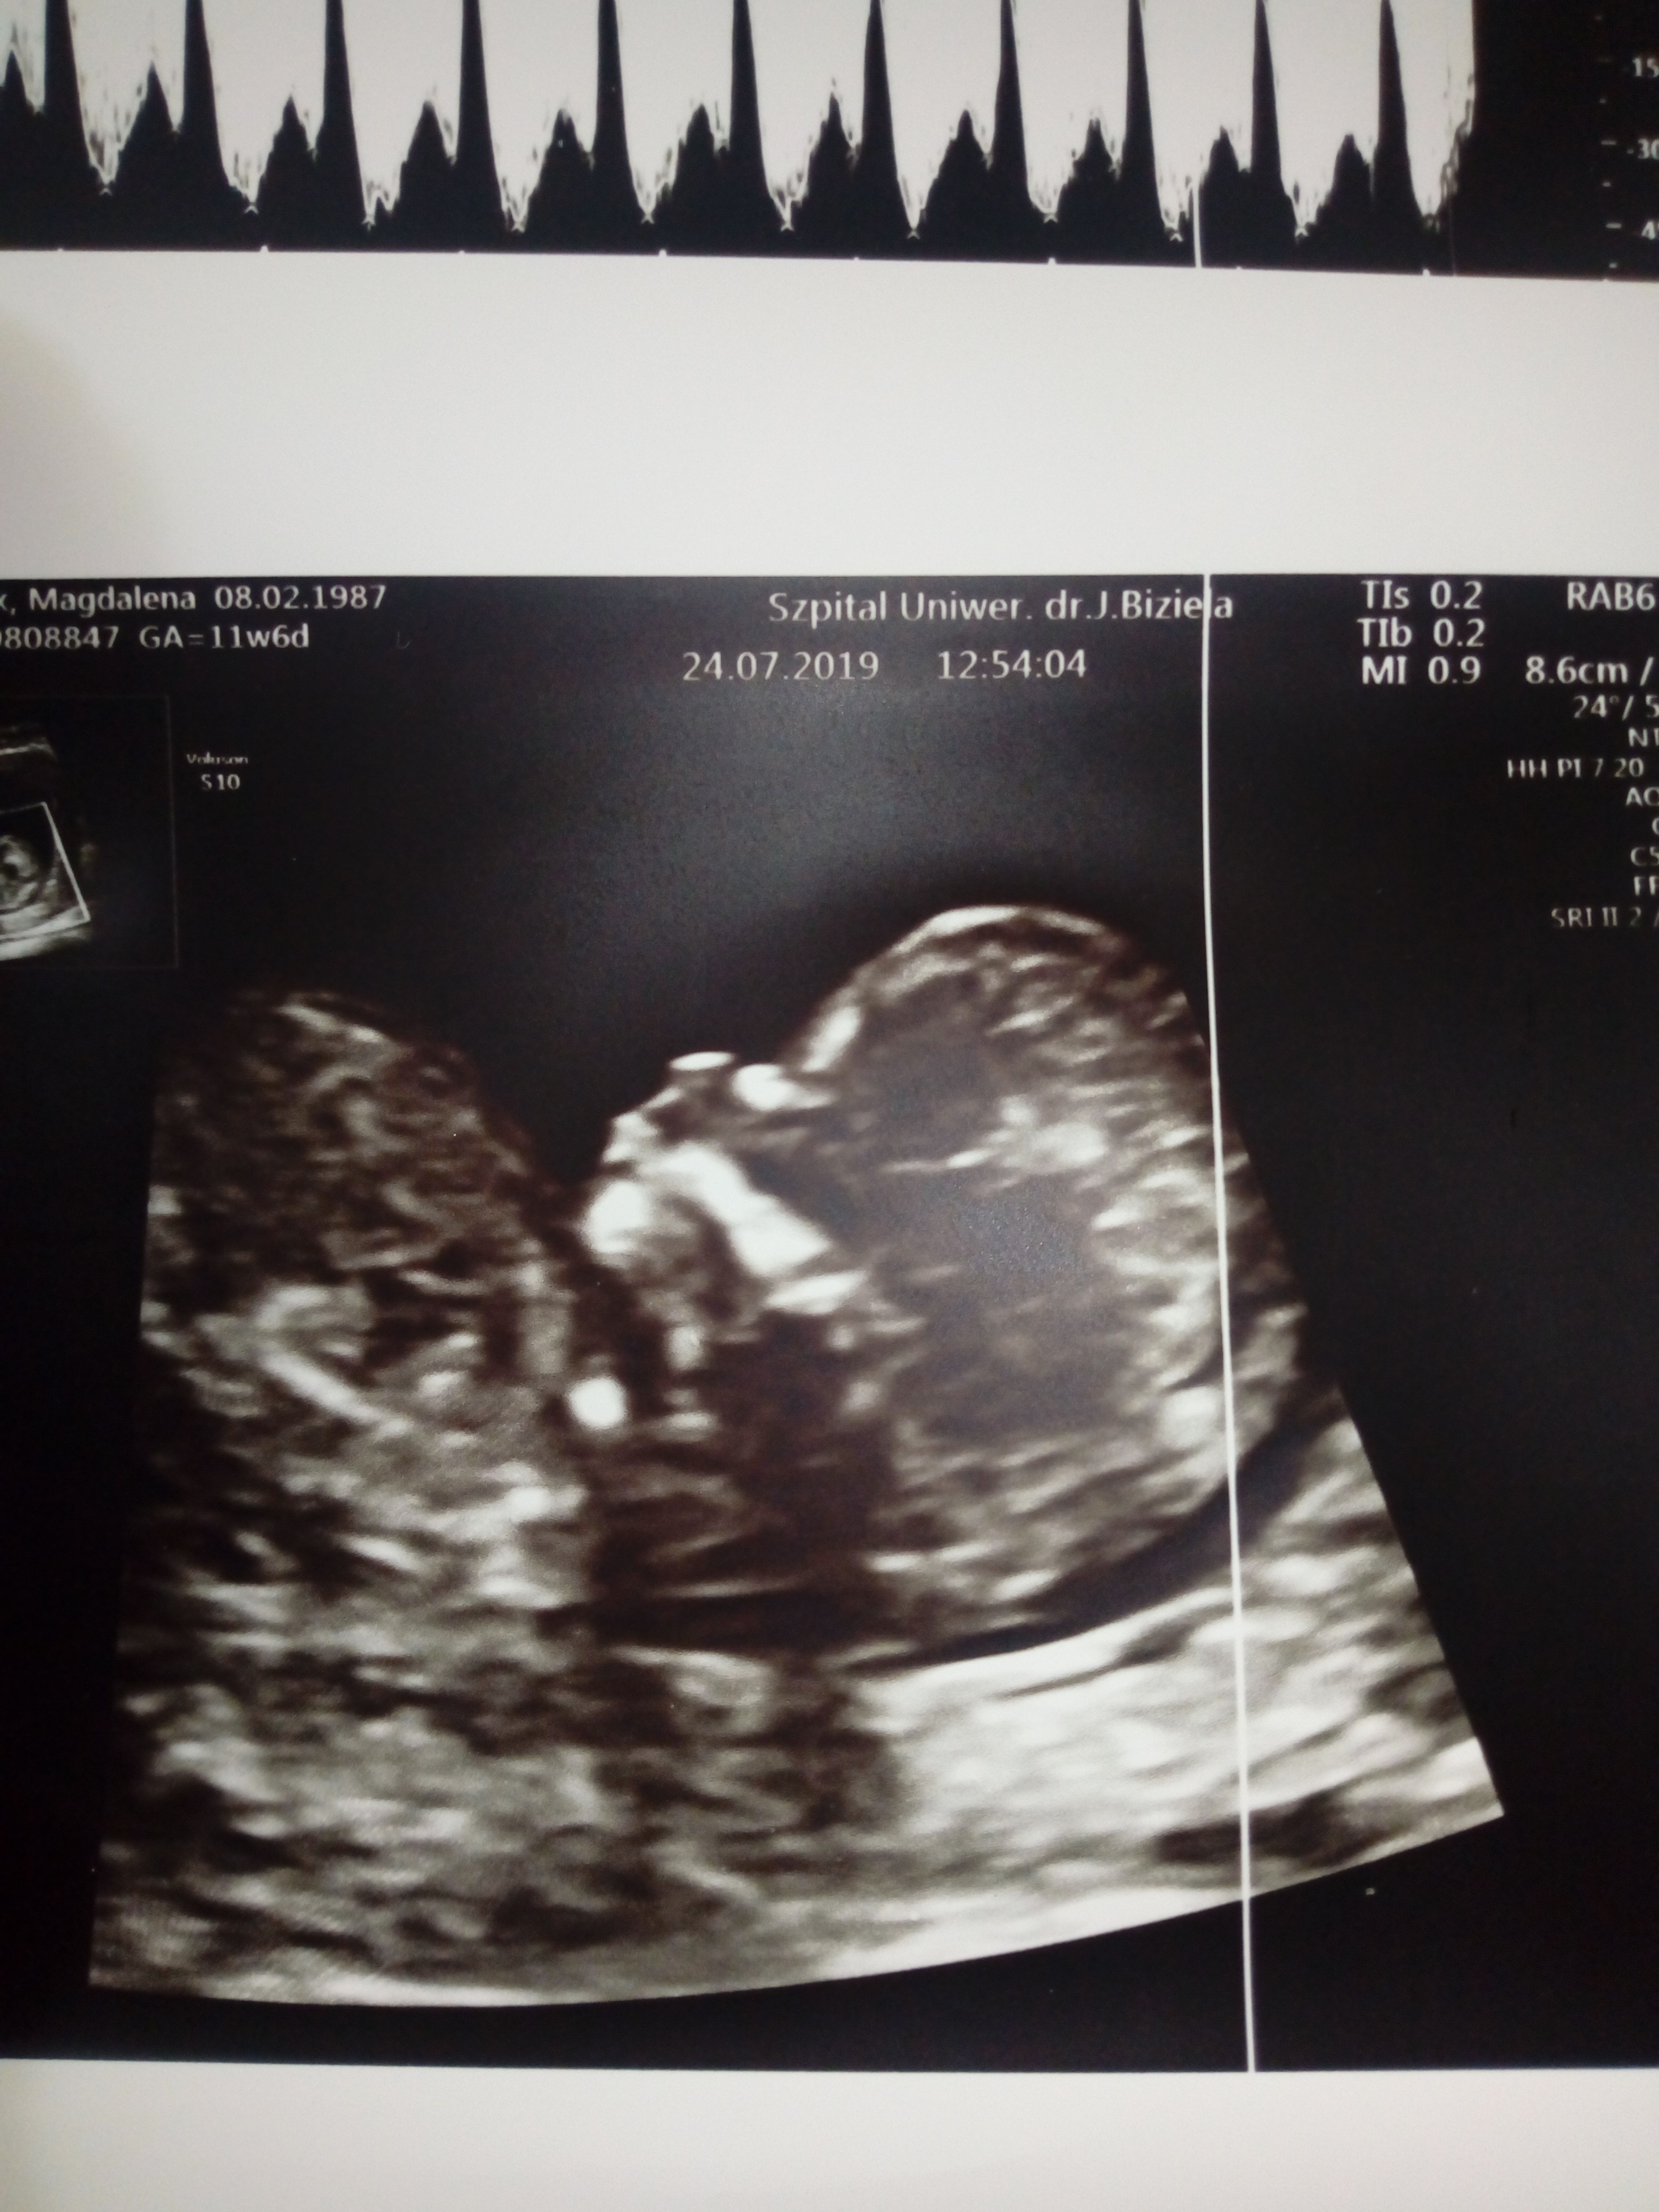

Cześć, znalazlam to forum po przekopaniu chyba całego netu w poszukiwaniu pomocy,rady,wsparcia?mam 32 lata,to moja 3 ciąża, z czego tylko jeden 7 mio latek w pelni zdrowy w domu, druga utracona w 7tc...Moj gin na rutynowej wizycie w 10 tc przyuwazyl NT rzędu 5,15 Kazal przyjechać po tygodniu gdzie NT wynioslo juz 2,4 Jednak mimo tego i jego zdaniem dobrego usg gdzie widzial kość nosowa,serce,narzady,rece,nogi wyslal mnie na prenatalne do Bydgoszczy do Biziela. Tam pani dr robila usg przez brzuch, przez pochwe i znowu przez brzuch bo male sie wiercilo Pomiary Nt wychodziły od 2,5 do 2,8 i tak w końcu wpisala Do tego obrzęk w okolicy karku plodu, Dv serca 1,29 Z uwagi na to WsZystko zalecila amnio ktore mam miec w dniu odbioru testu pappa po konsultacji z genetykiem....Boje sie tego badania poniewaz mam jelito drażliwe,od początku ciąży mam bóle brzuchu,zaparcia,skręty jelit...Mój gin mowi ze mogę zrobić test z krwi Nifty lub sanco Ale jeśli wyjdzie i tak wada to amnio mnie nie ominie jesli zdecyduje sie na terminacje ciąży...mam tydzień czasu na podjecie decyzji, przeczytałam większość wpisów tutaj Dziewczyny mowia ze badanie nic przyjemnego ale do przeżycia i u nich obylo sie bez powikłań...Doradzcie czy test z krwi Sanco czy amnio?

Usg prenatalne mialam juz we właściwym tyg czyli 11+6, Teoretycznie mam tylko opis badania usg ,ponieważ kolejka szla w,szpitalu w ten sposób ze najpierw mialam genetyka a potem po ok godzinie dopiero usg prenatalne wiec ryzyka oszacowanego typowo nie mam Zalaczam zdjecia dzidzi i opisu .Co do decyzji to została ona podjeta juz nawet przed ciążą,co by było gdyby....I moze zostanę zlinczowana przez kogos ale nie chodzi tu o mnie,o mój egoizm Myślę raczej całościowo Nie chce straszaka w przyszłości ewentualnie obarczac opieka nad chorym rodzeństwem...Poprostu nie...

W środę mam najpierw wyniki pappa, rozmowę z genetykiem i później ewentualnie amnio...Ja wiem ze nikt nie moze podejmowac decyzji za mnie Jestem tego świadoma